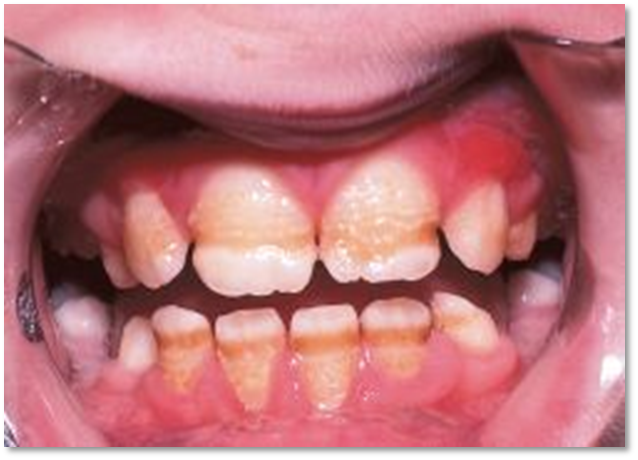

Amelogenesis Imperfecta (Figure 1)

Amelogenesis imperfecta (AI), a group of hereditary diseases affecting the tooth enamel in either quality or quantity, is associated with crown malformation and abnormal enamel density [6,7].

Hypoplastic Amelogenesis Imperfecta occurs due to defect in enamel matrix deposition, i.e., the first stage of enamel formation.Patients arepresents with thin enamel with yellowish-brown, rough or smooth, flat occlusal surfaces of the posterior teeth due to attrition, and with/without grooves and/pitting. The enamel will be thin, well mineralized and do not chip. Radiographically thin enamel but normal radiodensity will be seen. Defects in matrix formation with a disturbance in the differentiation or viability of ameloblasts will be seen in histology section [6,9].

In this type, Qualitative defect of the enamel is seen where the enamel is not sufficiently mineralized. The teeth are normal morphologically at the time of eruption, but eventually chip away posteruptively, especially in the occlusal areas. Clinically, the colour of teeth here varies from creamy opaque to marked yellow/brown. The surface of the teeth appear soft and rough leading to sensitivity due to dentinal exposure. Open bite malocclusion is a common feature. The enamel thickness is normal but often chips off and abrades away easily. Radiographically, there appears to be reduced differentiation between enamel and dentin which may be difficult to verify. Enamel has contrast similar to or greater than dentin, unerupted crowns have normal morphology radiographically.6,10

Hypocalcified Amelogenesis Imperfecta

Qualitative defect occurs when the enamel is insufficiently mineralized and soft. In comparison with hypo maturation type, the mineralization in this type is markedly reduced. Clinically, the crowns of the teeth appears to be opaque white to yellow-brown, soft rough enamel surface, dental sensitivity and very poor aesthetics. Due to severe hypomineralization, there may be early loss of enamel. The thickness of enamel appears to be normal at eruption that often chips and but, tends to abrade easily post eruptively. There may be delayed eruption of teeth. An anterior open bite of skeletal origin may be seen. Accumulation of a large amount of supragingival calculus is evident. There are two types, i.e., diffuse autosomal dominant (AD) and diffuse autosomal recessive (AR), with more severity in AR. Radiographically enamel is less radiopaque then dentin [9,10].

Hypomaturation-Hypoplastic with Taurodontism

Clinically, the crown appears to be white/yellow brown mottled. The teeth appear smaller than normal and they lack proximal contacts. In these cases, the enamel thickness is drastically reduced. The crowns show pitting and tend to have hypo mineralized areas. Radiographically, the enamel contrast is normal to slightly greater than dentin, and shows large or bulbous pulp chambers which appear taurodontic. In hypoplastic-hypomaturation with taurodontism, the enamel is thin, mottled yellow to brown, and pitted. Molar teeth exhibit taurodontism, and other teeth have enlarged pulp chambers [6,10].

Clinical Feature [6,9,10]

In the hypoplastic form, females show vertical ridging of the enamel, whereas, in males there is uniform hypoplasia.

In the hypomaturation form, males have teeth of normal size and shape, but with irregular, pigmented mottling. Females display vertical bands of mottling, often inconspicuous under normal lighting conditions.

Figure 1: Amelogenesis Imperfecta